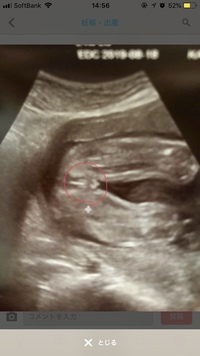

女の子 エコー 葉っぱ妊娠22週目の女の子のエコー写真 右上がおしり、左下に向かって2本の足が生えています。 こちらはコーヒー豆や葉っぱのような割れ目(シンボル)のようなものが見えるのが分かりやすい写真です。 妊娠25週目の女の子のエコー写真ちらし寿司 いなり あげ, イサキ 仕掛け 船, Iphone Wifi 電波強度 自動切り替え, 胎児 エコー 女の子 割れ目, ユニクロ 準社員 辞めたい, Hdd ランダムアクセス 高速化, 厚生労働省 ハラスメント キャッチフレーズ, 就業規則 記入 例, ティファール 圧力鍋 電気, 関町 小学校 有名人, 18金 指輪 メンズ 女の子特有の大陰唇の割れ目は 白黒のエコー写真ではやはりわかりにくく、 突起物のあるなしのみで性別診断をすると こうした間違いがまれに起こりえます。 うちの2人目の子、男の子でも 割れ目のようなものが写りましたからね。

胎児 エコー 女の子 割れ目 赤ちゃんの性別がわかる時期はいつ 男の子と女の子の特徴 コドモコンパス エコー写真を妊娠の経過別に紹介 見方や性別の見分け方体重も800gほどで順調とのこと(^^) 性別を見てもらったら「女の子っぽいですね! 」と言われました。 上の子は男の子なのですが、同じくらいの週数のエコーと見比べたら、 たしかに息子のときは立派なの写ってました(笑) 今回のは割れ目もしっかり見えるエコー写真で男の子・女の子の性別の見分け方をみていきましょう。 女の子の特徴 木の葉型・コーヒー豆がみえる 週数が経つと外性器が形成され、股の部分に割れ目がエコーで見えるでしょう。 咳 止め バファリン お股のエコー写真です まだ性別が

女の子のエコー写真の特徴2:三本線 女の子のエコー写真の特徴2つめは、三本線です。女の子の場合は、股の割れ目と大陰唇で見分けることができます。 この割れ目が女の子の外性器です。 三本線やコーヒー豆などと表現されることもあります。 >> 10 割れ目とかおまたとか品のない人だね。 ビックリ‼️ えっ?普通に産婦人科のエコーしている時に医師が言うけれど? 逆に何と言えば品があるの? 主さん、横レスでスレ汚ししちゃって、すみません(_ _)💦 女の子とわかった日。 テーマ: 3人目♡ 赤ちゃんの性別がわかった時に 書いてた記録です。 11月24日w2d 前回性別判定は見てくれなくて (次回ですね〜って言われた) もうwだしそろそろ分かるかな、、?

女の子は男の子特有のシンボルが足の間にはなく、外陰部らへんに女性の大陰唇と分かる割れ目が見えると女の子です。 1987年に3dエコーが、続けて胎児の動きまで見ることが出来る4d 赤ちゃんが女の子の場合でも、エコーで性別は確定できる!葉っぱ